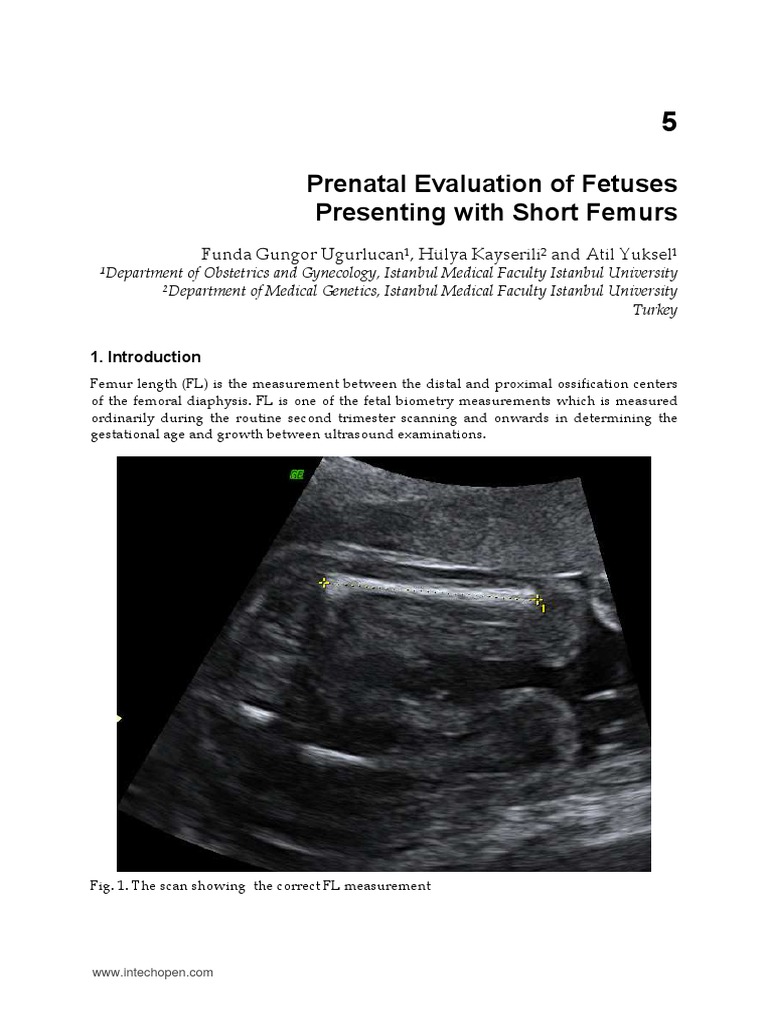

InTechPrenatal Evaluation of Fetuses Presenting With Short Femurs What Causes Short Femur Length In Fetus    a short femur length identified on ultrasound in the second or third trimester raises concern for certain conditions in. When the femur length is. Congenital short femur is a rare type of congenital malformation that occurs during prenatal.  what is congenital short femur?   diagnosis of isolated femoral shortening during the second half of pregnancy has so far. What Causes Short Femur Length In Fetus.